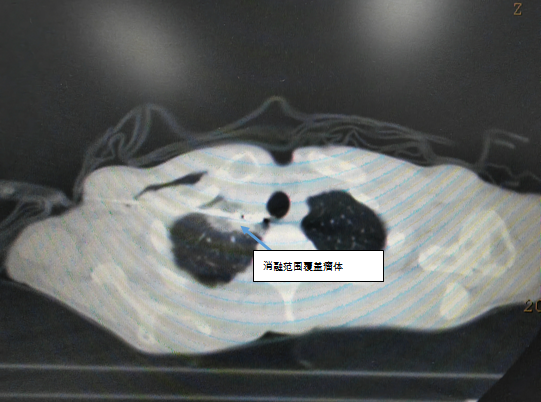

患者为60岁男性,右肺上叶腺癌伴多发转移靶向治疗中,入院前检查右肺上叶病灶较前增大,直径约2.3*1.5cm,为寡进展表现。对于靶向治疗中出现寡进展,指南推荐靶向治疗不变基础上行进展病灶局部治疗。同家属和患者充分沟通后,于2023年7月18日行CT引导下右肺上叶病灶微波消融术,手术过程完成。

CT引导下肺部肿瘤消融作为新兴的肿瘤微创治疗方法,已广泛运用于原发肺部肿瘤和转移肺部肿瘤的局部治疗,具有创伤小、精准、可重复、安全性高、患者恢复快等特点。对于无法耐受手术切除的早期非小细胞肺癌患者(肿瘤直径2-3cm)进行消融治疗,显示了该项技术在肺部肿瘤治疗中的价值。